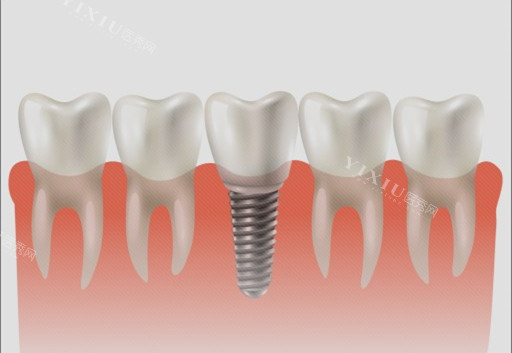

影响种植牙使用寿命的因素有很多。首先是患者自身的口腔条件。如果患者牙槽骨骨量充足、密度适宜,且口腔卫生状况良好,没有牙周炎等疾病,那么种植牙的稳定性和使用寿命会更有维持。

反之,若牙槽骨条件不佳,或者存在口腔炎症,就可能影响种植牙的成功几率和使用时长。其次,种植体的品牌和质量也至关重要。不同品牌的种植体在材料、设计和工艺上存在差异,优质的种植体通常具有更好的生物相容性和稳定性,能为长期使用奠定基础。